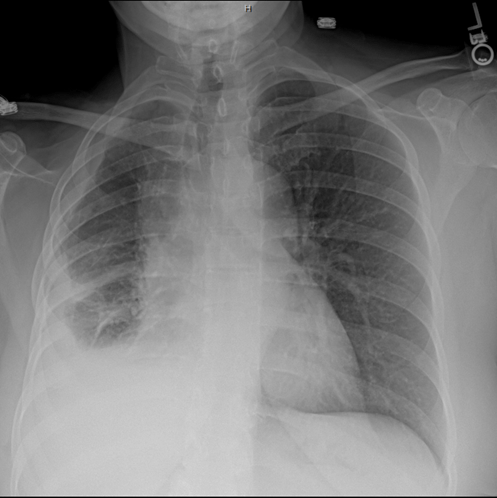

In the usa, nine out of every million individuals develop malignant mesothelioma, while in japan seven out of every million individuals develop . (a) CT chest showing pleural-based left upper lobe lung

(a) CT chest showing pleural-based left upper lobe lung from www.researchgate.net